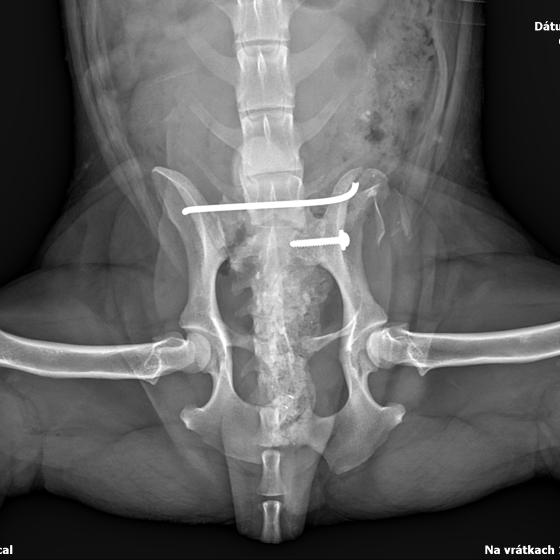

Karola nám doviezla pani, ktorá ho našla, asi jediná dobrá duša, ktorá pri ňom neprešla so zatvorenými očami. Ihneď sme s krpcom utekali na veterinu aby sa zistila závažnosť jeho zranení. Hneď pri prvých RTG snímkoch sa ukázala obojstranná fraktúra panvy, taktiež fraktúra krídla panvy a keby mu to chudákovi nestačilo, do tretice sa objavila zlomenina stavca. Karolko mal neznesiteľné bolesti, ale krásne prečkal vyšetrenie lebo vedel, že je v dobrých rukách a dostáva sa mu pomoci. Po nálezoch sme okamžite kontaktovali neurológiu a ortopédiu na veterinárnej klinike Sibra - centrum veterinárnej medicíny, kde sme dostali hneď termín na príjem.

Karol nemá žiadne neurologické deficity, po ortopedickej operácii bude vedieť behať a bez problémov bude vedieť samostatne cikať a kakať. Po tejto úžasnej správe sme samozrejme dali zelenú náročnej ortopedickej operácii pod vedením MVDr. Vatolíka. Operácia sa podarila na výbornú, Karči je "zoskrutkovaný" a vôbec nič mu nebráni v tom, aby opäť mohol behať a aktívne žiť. Momentálne sa zotavuje po operácii, musí mať prísny kľudový režim. Po vybratí stehov ho čaká hydro- a fyzioterapia, ktorá mu pomôže postaviť sa na nohy. Je to bojovník, veľmi sa chce uzdraviť a v jeho očkách je dokonale vidieť, že už kuje plány čo všetko zameškané bude musieť dobehnúť.